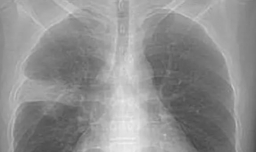

白肺意味着什么 严重吗

白肺的一个明显表现是气紧还有呢

肺部变白是不是没救了 肺部变白是肺部纤维化吗